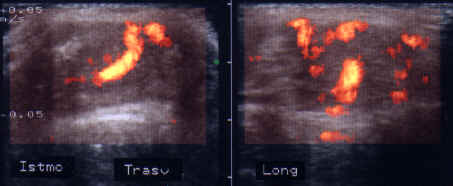

ecocolordoppler si powerdoppler- acelasi nodul

Vascularizatie interna, mai evidenta in powerdoppler.

Femeie 25 ani. Nodul unic in lobul stang, contur net, hipoecogen, respecta parenchimul din jur, neomogen, de 18x23x36 mm (7,5 cc).

Citoaspiratia cu ac subtire: nodul adenomatos.

Examen histologic postoperator: adenom trabecular fetal.

Acelasi caz. La doppler color - vascularizatie interna, mai evidenta in powerdoppler.